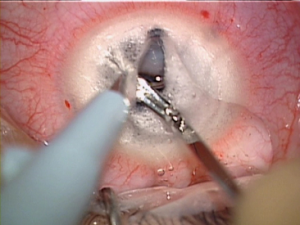

- C) Transplante de Córnea no Tratamento do Ceratocone

O transplante de córnea é uma cirurgia que substitui a córnea doente por outra saudável.

Dr. Gustavo Bonfadini, relata que o objetivo é sempre tentar evitar o Transplante de Córnea no paciente com Ceratocone. Porém caso seja necessário a técnica cirurgica recomendada é o Transplante de Córnea Lamelar Anterior, onde as camadas externas da córnea são substituídas.

Os casos de Ceratocone que progredirem para onde a correção visual não pode ser mais atingida com óculos e lentes de contato ou quando o afinamento da córnea se torna excessivo ou ainda em casos onde existam cicatrizes de Córnea (por Hidrópsia, Infecções, Traumas ou Distrofias) ou exista a presença de leucoma (opacificação corneana importante), o Transplante de Córnea se torna necessário.

A Ceratoplastia Lamelar é uma técnica cirúrgica de Transplante de Córnea utilizada no tratamento de patologias que afetam a região anterior e estroma médio corneano. É um procedimento extra-ocular que oferece uma adesão tecidual eficiente no pós-operatório imediato e reabilitação visual rápida, com mínimo risco de rejeições e outras complicações a longo prazo em comparação com o transplante de córnea com espessura total da córnea convencional.

O mais recente avanço para o tratamento cirúrgico do Ceratocone em transplante é o refinamento da técnica de Transplante de Córnea de espessura total (Transplante Penetrante) por um Transplante de espessura parcial (Transplante Lamelar). Trata-se do implante da córnea mantendo o endotélio do paciente. Com a nova técnica, é possível que esses pacientes recuperem a capacidade visual com menor risco de rejeição.

– Ceratoplastia Lamelar Anterior Profunda (DALK)

Segundo o Dr. Gustavo Bonfadini, especialista nesta técnica cirúrgica e desenvolvedor de material cirúrgico para melhorar o resultado desta técnica: “O Transplante Lamelar Anterior Profundo é realizado, preservando-se a camada interior da córnea – chamada de endotélio. Essa técnica é importante, por diminuir a probabilidade de rejeição e melhorar os resultados quando comparada a técnica cirúrgica tradicional.” Retira-se somente o estroma corneano (a parte doente da córnea), mantendo-se a membrana de Descemet e o Endotélio. A técnica conhecida como “Big Bubble”, na qual se separa a membrana de Descemet do estroma utilizando uma bolha de ar é a mais utilizada.

A técnica conhecida como “Big Bubble” (Grande Bolha), é mais difícil de ser realizada, mas representa uma boa opção quando a parte interna da córnea (endotélio) está saudável.